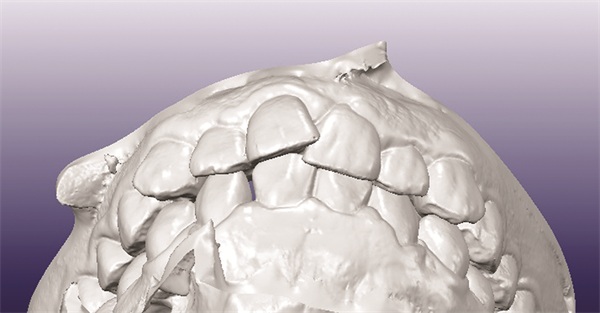

Records showed oversized maxillary incisors, canines, and premolars, with a Bolton discrepancy of 13.4 mm excess in the upper anterior segment and 9.5 mm overall (Figs. 1–6). The original poster anticipated needing digital setup models and suspected upper premolar extractions might be required. The central question posed to the forum was straightforward: How should this case be treated?